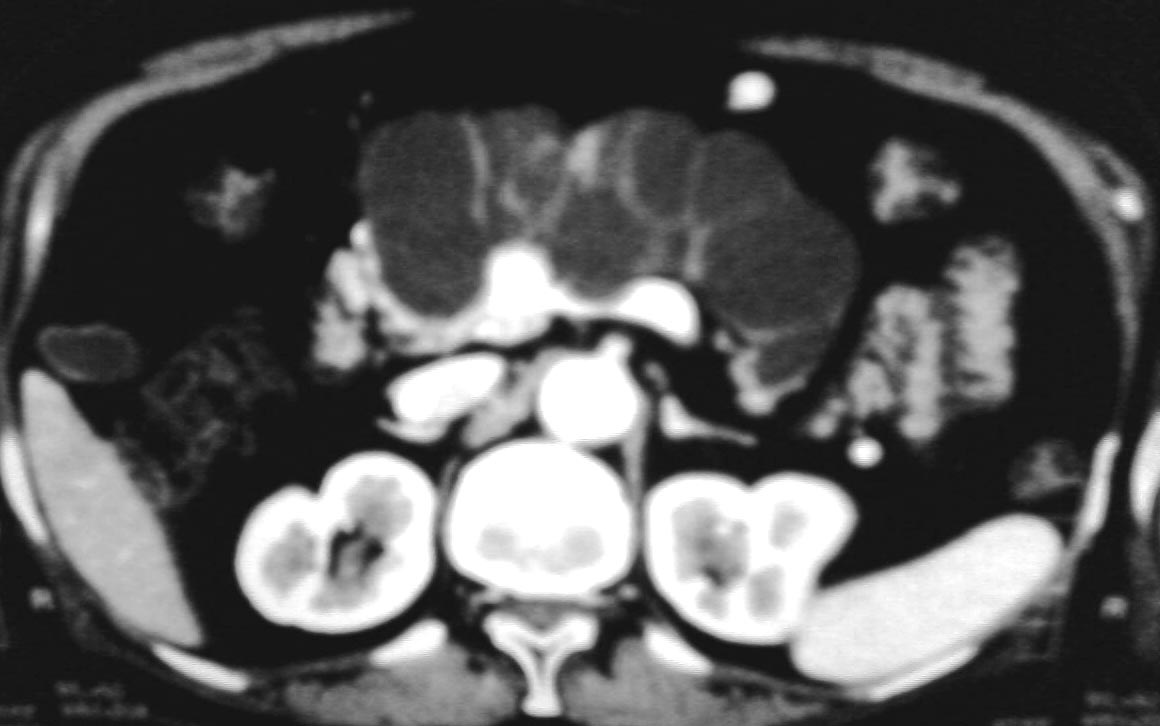

上腹部不适半年左右,体检此区压痛,精神状态很好,谢各位给个意见!

与中国医学影像网中“今日病例”(12-2)类似——胰管乳头状粘液瘤。

考虑胰腺黏液腺癌.低度恶性.

考虑胰管乳头状粘液瘤

胰腺占位病灶

1与中国医学影像网中“今日病例”(12-2)类似——胰管乳头状粘液瘤

2考虑胰腺黏液腺癌.低度恶性.